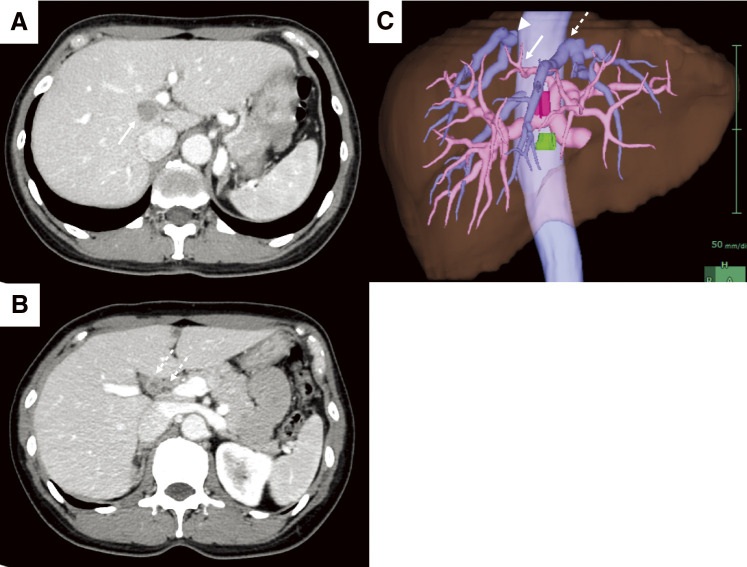

CASE PRESENTATION: A 52-year-old woman was referred to our hospital and was subsequently diagnosed with bilateral breast cancer. Computed tomography (CT) and magnetic resonance imaging incidentally detected a liver tumor in the hilar region and lymph node enlargement in the hepatoduodenal ligament. A 19 mm tumor was observed in the area surrounded by the right and left branches of the portal vein and an abnormal portal branch of segment 7. Positron emission tomography-CT showed fluorodeoxyglucose uptake in the liver tumor, hepatoduodenal ligament lymph nodes, and bilateral breasts. A tumor biopsy showed a papillary tumor, and ICC was suspected. As ICC with LNM has a poor prognosis, neoadjuvant chemotherapy was planned. Genetic testing using a blood sample revealed a BRCA2 mutation, indicating the patient would benefit from chemotherapy, particularly cisplatin. The patient received a chemotherapy regimen comprised of gemcitabine, cisplatin, and S-1 (GCS), and after 7 courses, her carbohydrate antigen 19-9 level decreased from 2433 to 15 U/mL. CT showed that the tumor had shrunk and the LNMs were indistinct. The patient was referred to our department for curative surgery, which included a left hepatectomy, caudate lobectomy, hepatoduodenal ligament lymph node dissection, bile duct resection, and choledocojejunostomy. The postoperative course was generally uneventful, and the patient was discharged on postoperative day 18. Pathological examination of the resected specimen revealed an absence of malignant cells. At 24 months postoperative, there was no evidence of recurrence.